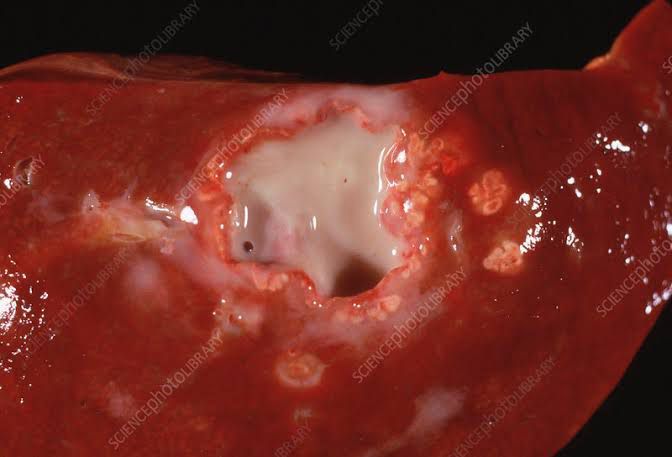

There are many possible causes of liver abscesses, including: Abdominal infection, such as appendicitis, diverticulitis, or a perforated bowel Infection in the blood Infection of the bile draining tubes Recent endoscopy of the bile draining tubes Trauma that damages the liver